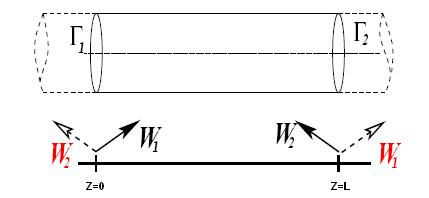

1.2.1.4 Aortic Coarctation

Aortic coarctation(CoA) occurs approximately in 10% of patients with congenital heart defects and represents a narrowing of the descending aorta (see paper 1). Due to the reduction in the aorta descending diameter, high pressure gradients can appear across the CoA, resulting in an increased cardiac workload in the left ventricle during systole [57]. The narrowing of the aorta creates a flow jet with high velocity, inducing a very complex turbulent flow field. Recently, researchers has characterized changes of hemodynamic parameters such as pulse blood pressure, aortic capacitance, and wall shear stress due to the presence of an aortic coarctation [57][58][59]. Hemodynamic changes caused by the coarctation can result in endothelial dysfunction [60], provoking non normal values of TAWSS or elevated OSI for CoA patients.

From the methodology point of view, a new methodology to compute diagnostic indicators based on computational hemodynamics has been proposed. In order to compute the pressure drop under different patient-specific situations, a reduced-order model has been developed in paper 1. The reduced-order method was implemented as part of the C++ finite element library KRATOS[61]. KRATOS is a multiphysics simulation open source (LGPL licence) framework based on the stabilized Finite Element Method for analysis of the Navier-Stokes equations in viscous flows. Efficient and parallel solvers for 3D fluid problems have been implemented in KRATOS that allow tackling large problems using supercomputers if available. The 1D model developed in this monograph was also implemented as new elements inside KRATOS. Blood was modeled as a Newtonian fluid with constant density and different outlet conditions were implemented. In appendix 9 a detail description of the implementation is shown.

Boundary conditions from multiscale modeling of circulation: Another approach to impose the boundary conditions is to use reduced models, as 1D model or 0D (lumped) models. 1D and 0D models are mathematical models able to reproduce the systemic and pulmonary circulation. Figure 10 shows a standard approach to provide realistic local boundary conditions for 3D CFD simulations at the specific arterial domain using 1D models of the entire arterial tree and 0D models at the distal ends[83]. 1D model solves the Navier-Stokes equations under some assumptions (see appendix 9) and lumped models (0D models) can be derived from electrical circuit analogies where blood flow is represented by the current and arterial pressure by the voltage. Usually the electrical components of these circuits are resistances, inductances and capacitors. Where resistances represent arterial and peripheral resistance that occur as a result of viscous dissipation inside the vessels, capacitors represent volume compliance of the vessels that allows them to store large amounts of blood, and inductors represent inertia of the blood[75]. The values of these electrical components can be estimated from physical data of the subject [84][85]. This approach is quite used because it is capable to account for the effect of local pathological conditions on the whole circulatory system, providing realistic boundary conditions for the 3D problem [75][79][86].

Scientific contribution: Design of a new methodology to estimate the pressure drop in aortic coarctation under different scenarios. The methodology is based on the integration a 1D numerical model (see appendix 9) into a reduced order model based on 3D CFD formulation.

Contribution to the paper: The principal author developed and implemented the 1D model and the reduced order model into the KRATOS Multi-Physics software (www.cimne.com/kratos)([61]).